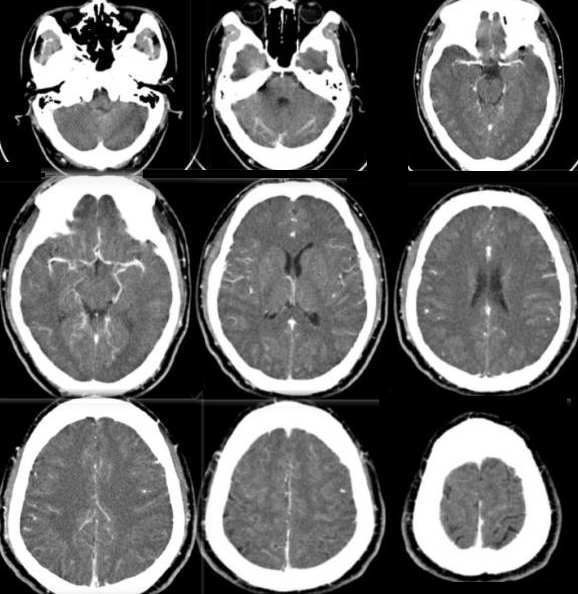

1:横扫+c:见两侧顶叶脑沟裂增宽加深。

综上考虑:顶部脑血管畸形以avm可能性大。并两侧顶叶局限性缺血性脑萎缩

顶部颅板下见弧形走行粗大血管影,明显强化,内见迂曲血管及脑实质影,其内脑实质较周围脑实质强化为著,周围未见水肿征象。轴位片未见明显异常。cta示顶部迂曲血管影增多、增粗,以左侧尤为明显。考虑脑血管畸形可能性大。本例需与以下疾病鉴别:①海绵状血管瘤:病灶局限,内可见斑点状钙化而不可见脑实质影,强化时间较常。②硬膜外血肿:边界清晰,内部不见血管影,周围不见异常血管。